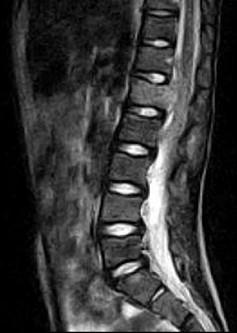

问题 女,9岁,背部隐痛,发热1个月余,MRI检查如图,请选出最可能的诊断 ( )

选项 A、脊椎结核伴硬膜外脓肿 B、椎体压缩骨折 C、脊柱转移瘤 D、硬膜下血肿 E、化脓性脊柱炎

答案 A